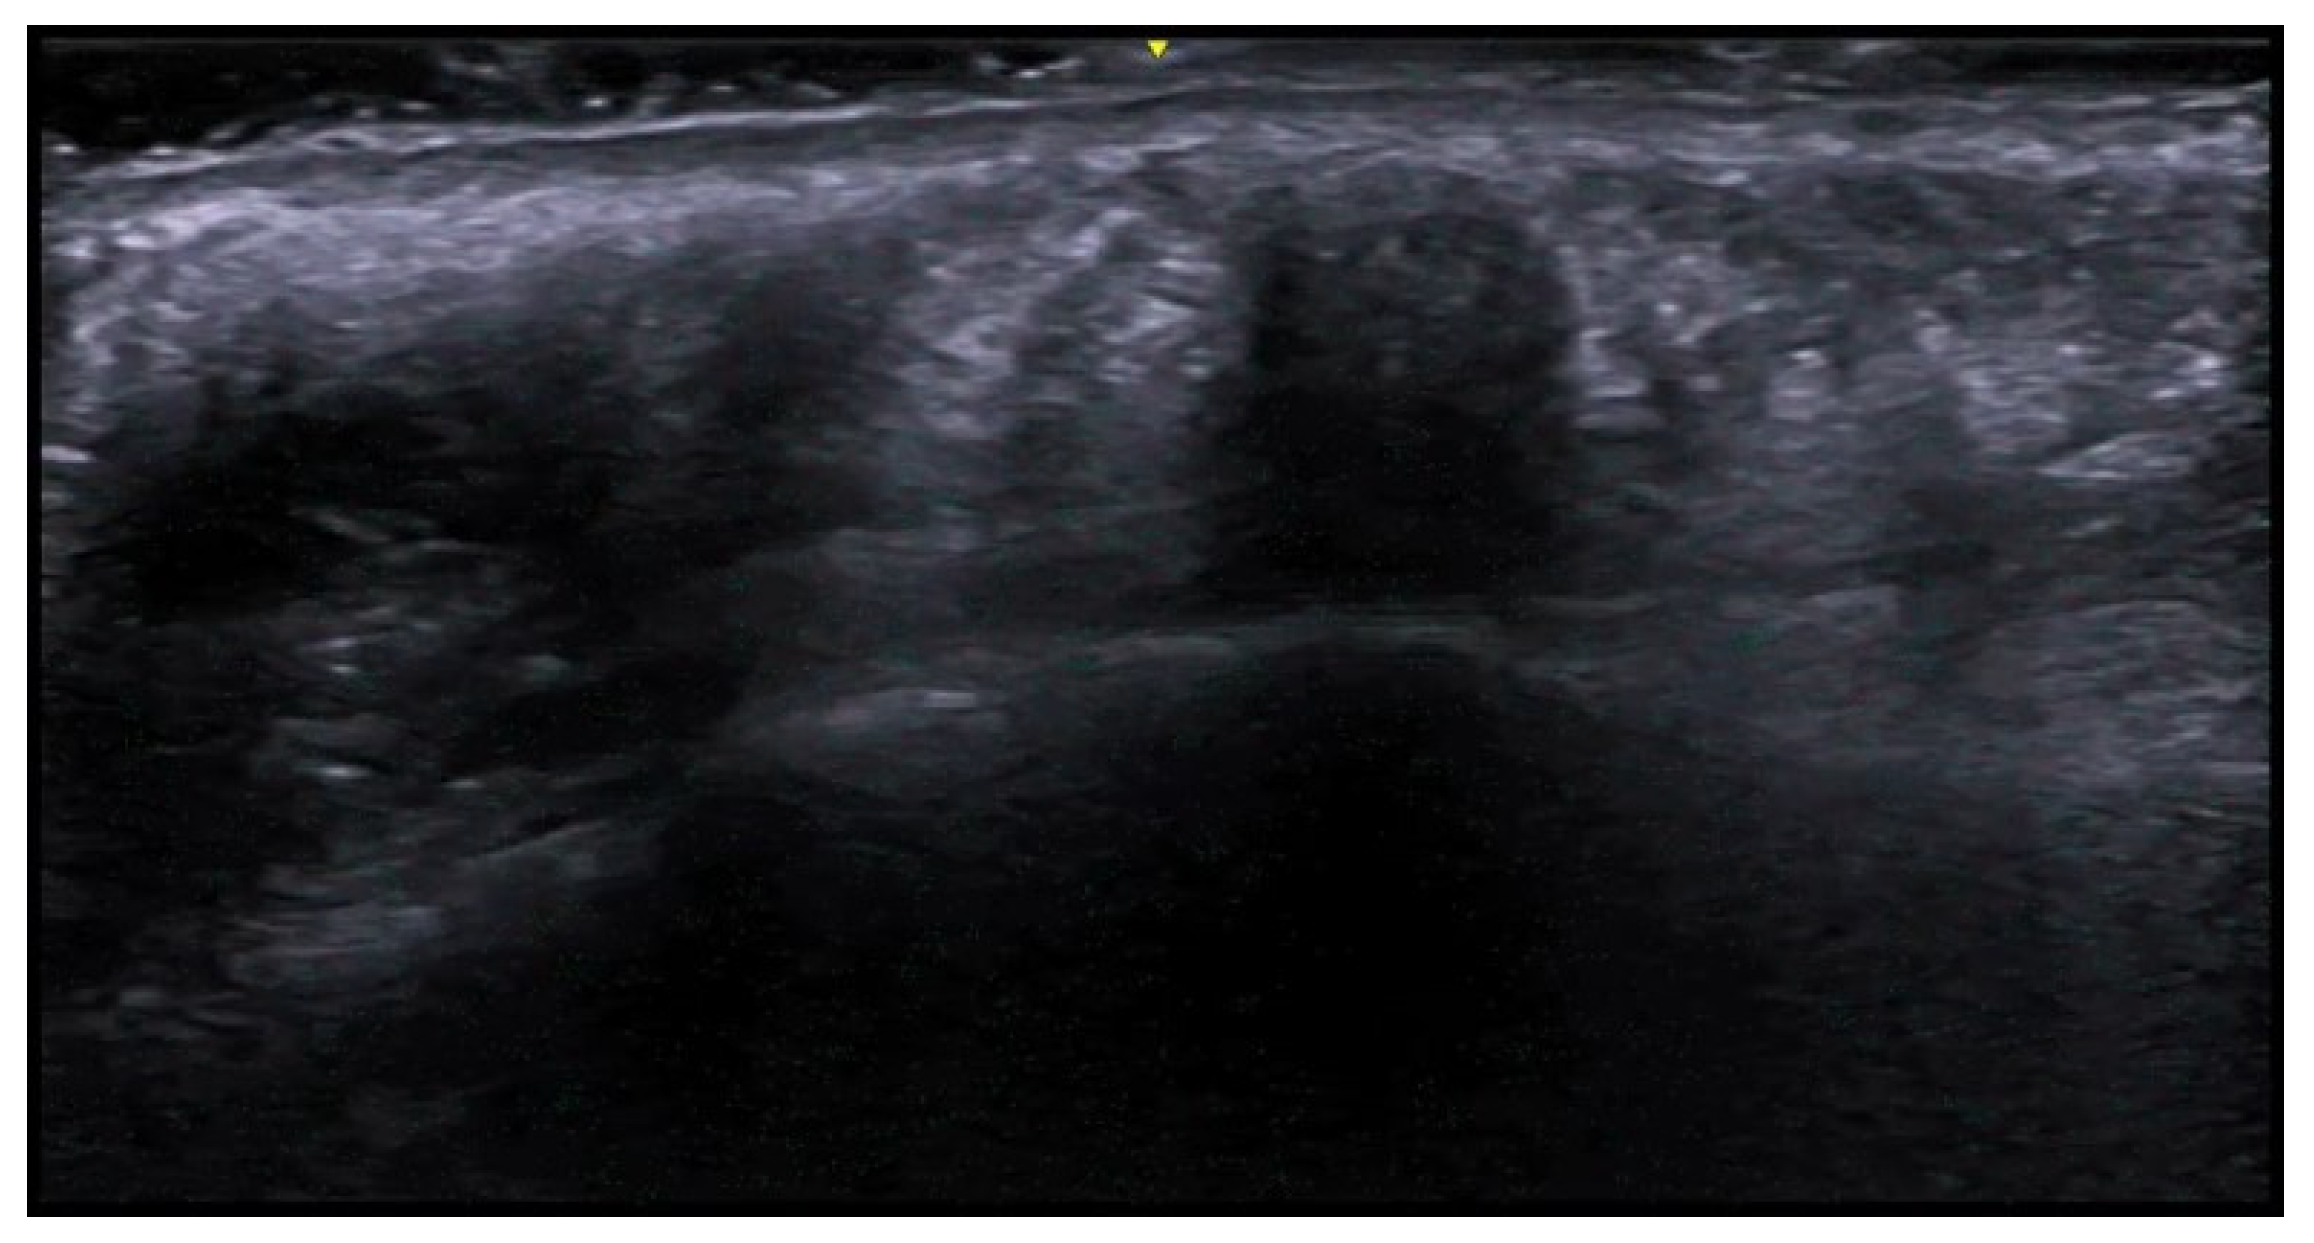

5. Specific Cutaneous Structure and Sites of Skin Disorders